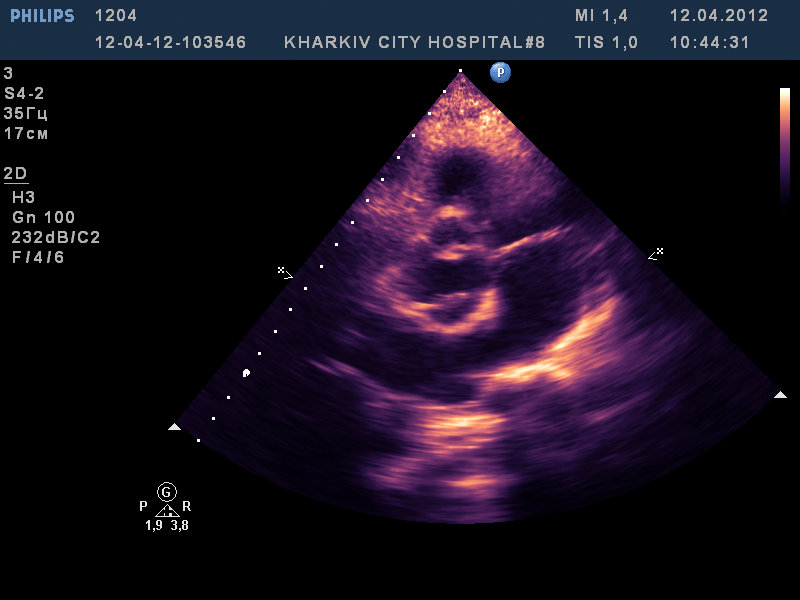

Парень 22 лет/

двухстворчатый аортальный клапан с выраженной аортальной недостаточностью, расширение восходящего отдела аорты до 4,2см, пролабирование передней створки МК III степени с незначительной регургитацией, дилатация левых полостей (КДР 6,6 КСР 4,5 ЛП 4,2), гипертрофия левого желудочка.

На видео видно двухстворчатый аортальный клапан с неполным смыканием створки с выраженной регургитацией (высокоскоростная струя под углом ударяет в переднюю створку митрального клапана вызывая пролабирование).